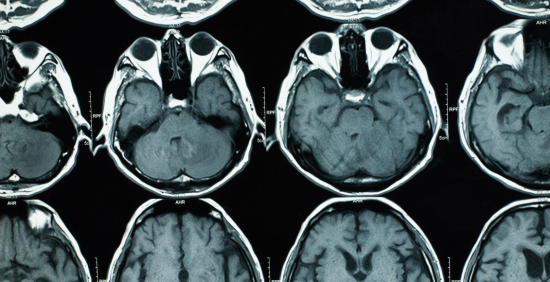

Neuroimaging is a way of taking pictures of the brain to see how it works. Researchers use specialised techniques and different kinds of scanners to learn more about mental health. Neuroimaging also helps to diagnose conditions and see how treatments are working.

Neuroimaging comprises techniques such as magnetic resonance imaging (MRI), Positron emission tomography (PET) and electroencephalography (EEG to study the brain).